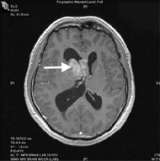

Pre Operative RMI Ependymoma

A pre-operative MRI image (above) shows an ependymoma (arrow) in the right lateral ventricle.

Ependymomas are tumors that arise from a thin layer of cells that line the ventricular walls and central canal of the spinal cord.